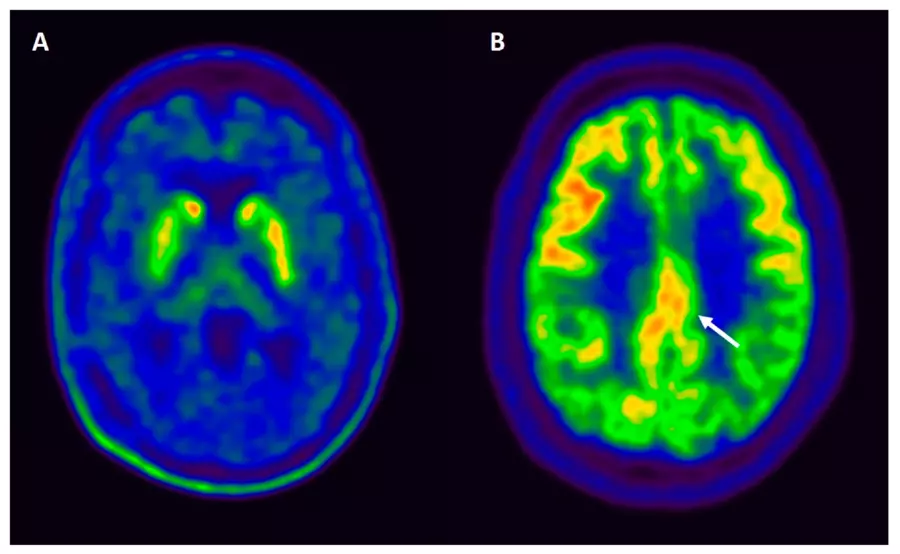

FDG PET scans look at how the brain uses glucose for energy. How well glucose is metabolized (processed) can affect cognitive function. In these scans, healthy brain metabolism appears blue and black, while impaired metabolism, such as in Alzheimer’s dementia, shows up as yellow, green, or red.